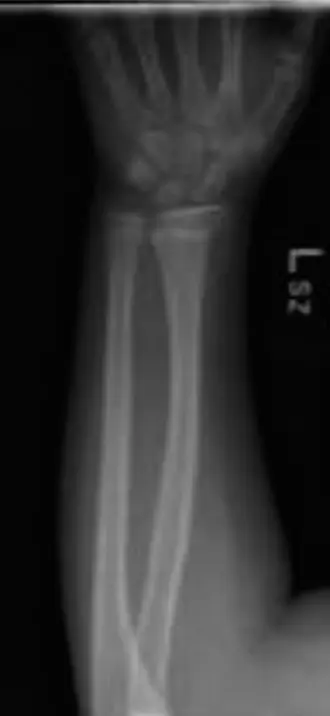

من الناحية السريرية، يشتكي الأطفال المصابون بكسر الالتواء من ألم موضعي وتورم وحساسية عند اللمس، ولكن عادةً لا توجد تشوهات واضحة أو مشاكل في الأعصاب أو الأوعية الدموية. عند التصوير بالأشعة السينية، تتميز هذه الكسور بانتفاخ طفيف أو انحناء في القشرة العظمية، ويُرى غالبًا بوضوح أكبر في الصور الجانبية لعظم الكعبرة السفلي.

• الصور القياسية: سيتم أخذ صورتين قياسيتين على الأقل للرسغ: صورة أمامية خلفية (AP) وصورة جانبية (Lateral). من المهم التأكد من أن الصور تشمل عظم الكعبرة والزند بالكامل.

• علامات كسر الالتواء: غالبًا ما يكون الكسر دقيقًا ويظهر كـ "انتفاخ" أو "تجعد" طفيف في قشرة العظم، ويُرى غالبًا بشكل أوضح على القشرة الظهرية في الصورة الجانبية. قد تكون الصور المائلة مفيدة في الحالات غير الواضحة.